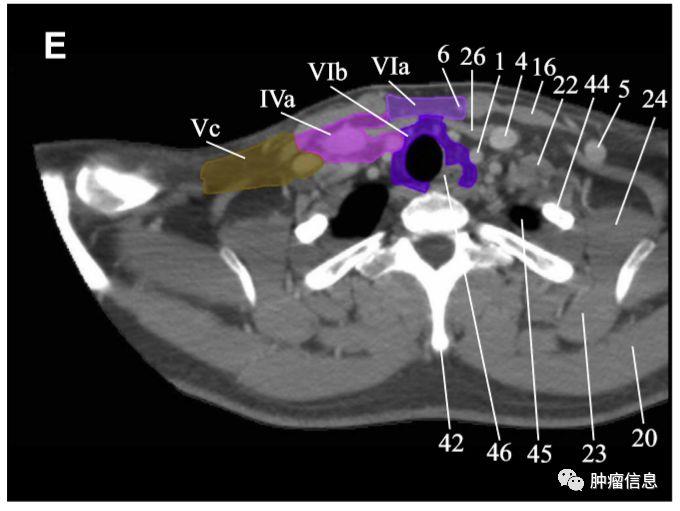

RTOG2013年头颈部淋巴结分区勾画图谱:

Ia:颏下淋巴组Ib:颌下淋巴组II:上颈淋巴组III :中颈淋巴组IVa:下颈淋巴组IVb:锁骨上内侧组V:颈后三角淋巴组Va:上颈后三角淋巴组Vb:下颈后三角淋巴组Vc:锁骨上外侧组VI:颈前淋巴组VIa:颈前淋巴结VIb:喉前、气管前、气管旁淋巴结VII:椎前淋巴组VIIa:咽后淋巴结VIIb:茎突后淋巴结VIII:腮腺淋巴组IX:面颊淋巴组X:颅底后组Xa:耳后、耳下淋巴结Xb:枕淋巴结见下图:

颈部VI区淋巴结

颈前淋巴结上界:舌骨下界:胸骨切迹后界:颈动脉鞘前方

颈部VI区图中紫色区域为VI区(VIa、VIb)

颈部VII区淋巴结

上纵隔淋巴结上界:胸骨上窝下界:主动脉弓上缘两侧界:颈总动脉

颈部VII区Ⅶ区淋巴结位于上纵隔(上纵膈淋巴结)。